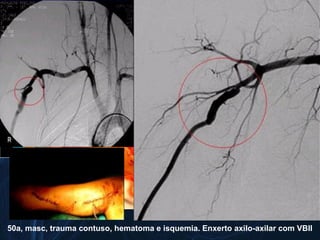

50a, masc, trauma contuso, hematoma e isquemia. Enxerto axilo-axilar com VBII

50a, masc, traumacontuso, hematoma e isquemia. Enxerto axilo-axilar com VBII